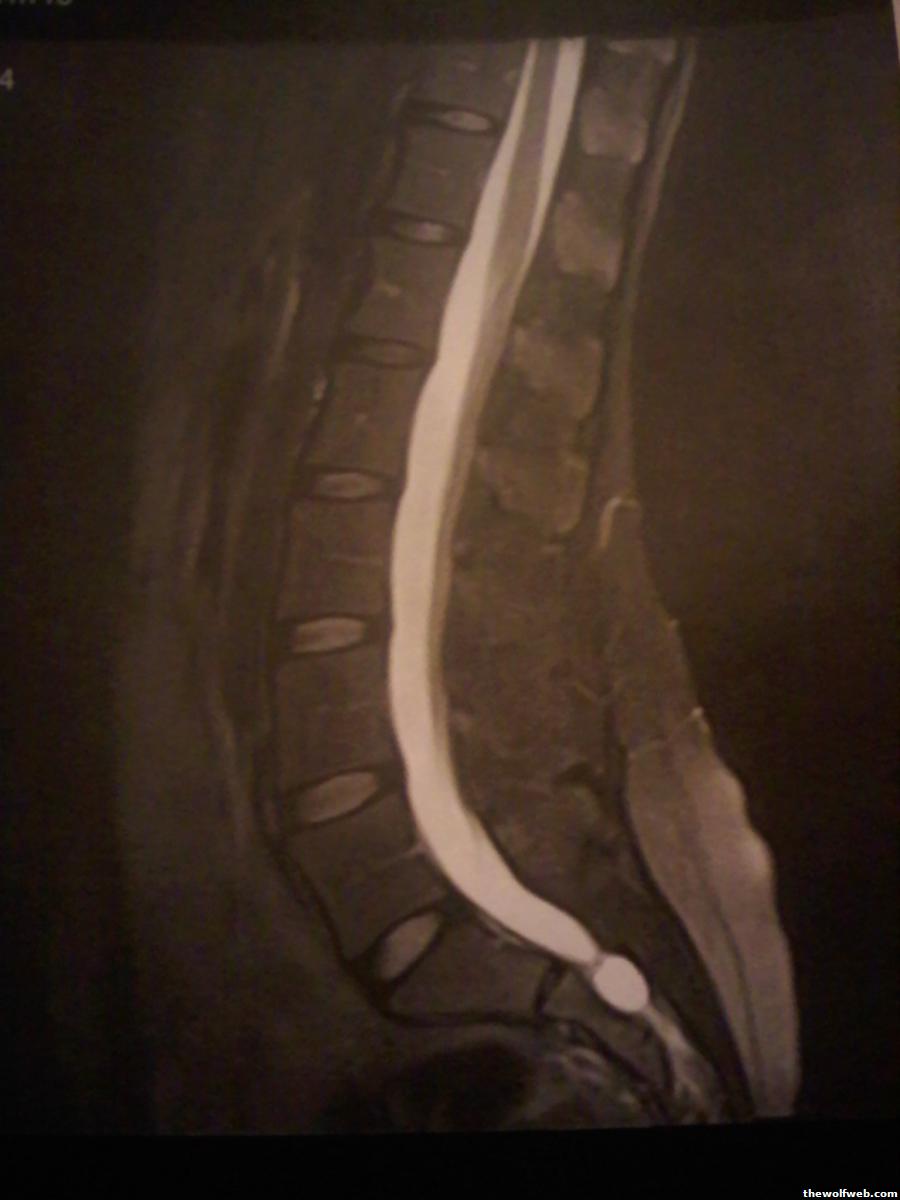

Eek